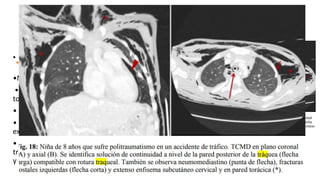

• A – C TAC prequirúrgica

15 días tras lesión 

interrupción bronquio

izquierdo principal;

• D broncoscopía

fibróptica – estenosis

por granulación.

• E RX posquirúrgica con

expansión pulmón

izquierdo.

• A –C TAC prequirúrgica 15 días tras lesión  interrupción bronquio izquierdo principal; • D broncoscopía fibróptica – estenosis por granulación. • E RX posquirúrgica con expansión pulmón izquierdo.